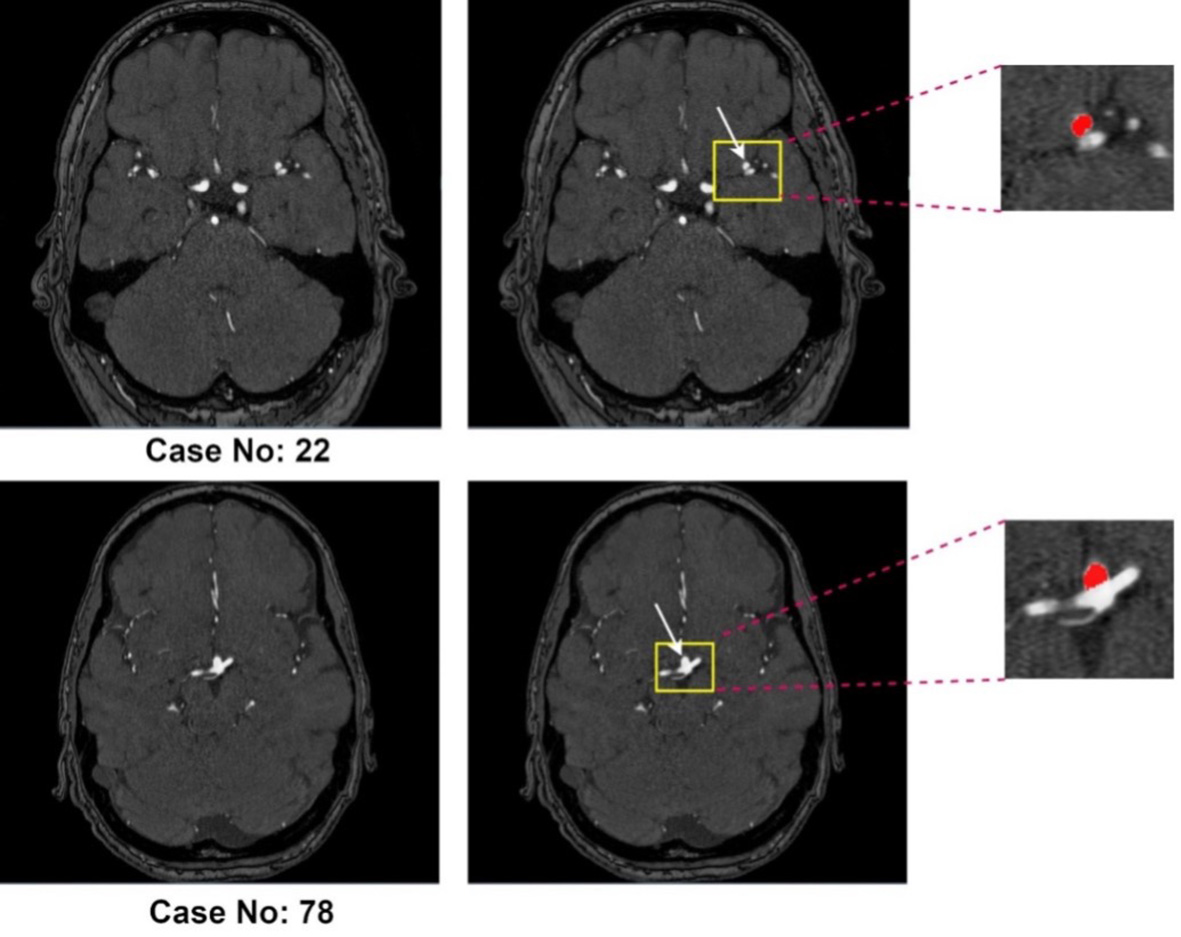

Approximately 3% of the global population harbors an unruptured intracranial aneurysm (UIA)[1]. In high-risk groups, particularly those with a positive family history of aneurysmal subarachnoid hemorrhage (aSAH), the prevalence increases to about 10%[2]. Rupture of an intracranial aneurysm leads to aSAH, a severe form of stroke associated with high morbidity and mortality: roughly one-third of patients do not survive and another third are left with permanent, life-altering disabilities[3]. Early and accurate detection of UIAs during screening is therefore crucial for assessing rupture risk and guiding management. Evidence from large observational cohorts indicates that factors such as aneurysm size, location, and morphology - including irregular shape and daughter sacs - are associated with increased rupture risk[4-6]. Current practice generally recommends preventive treatment for aneurysms with high predicted rupture risk, while lower-risk aneurysms are managed with regular imaging follow-up to monitor for growth, which itself is a strong predictor of rupture[4,7]. This approach allows clinicians to make more informed treatment decisions based on individualized risk assessment. With the increasing availability and quality of cerebral vascular imaging, incidentally discovered UIAs have become more frequent, leading to a greater need for reliable follow-up imaging[8]. The most commonly used techniques for UIA monitoring include contrast-enhanced computed tomography angiography (CTA) and non-contrast three-dimensional (3D) time-of-flight magnetic resonance angiography (TOF-MRA), with TOF-MRA being particularly suitable for routine surveillance because it avoids intravenous contrast agents and ionizing radiation[9-11]. Figure 1 illustrates two representative TOF-MRA cases with annotated intracranial aneurysms from the Aneurysm Detection And SegMentation (ADAM) dataset (Case 22 and Case 78).

Figure 1. Representative 3D TOF-MRA cases from the ADAM dataset. Case No. 22 (top row) and Case No. 78 (bottom row) both include intracranial aneurysms (highlighted in yellow boxes and magnified on the right, with the aneurysm mask shown in red).